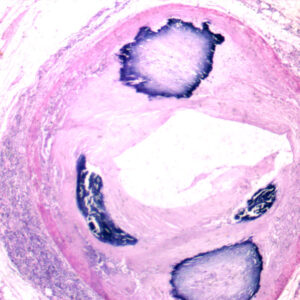

The Pathology teaching slides we offer are professionally hand-mounted, accurately stained, and individually labeled. Our microscope pathology slides are great for medical students, It has an excellent introduction to human disease in microscopy. The Pathology teaching slides are cover-slipped and preserved in cedarwood oil. All slides are carefully labeled for easy reference and are arranged in a fine plastic box with a separator. This pathology teaching slide set includes 14 systems of human diseases. It is excellent for educational use and is perfect for all levels of medical student study including home school programs.

What’s included in this 100pcs pathology teaching slides set: